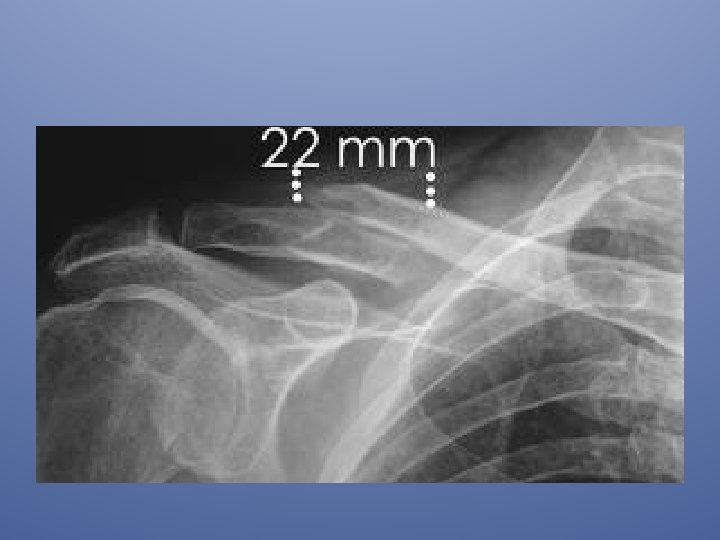

• les traitements chirurgicaux des fractures du tiers moyen de la clavicule étaient réservés aux cas suivants: • . fracture ouverte • fracture comminutive menaçante pour la peau • patient polytraumatisé, dans le coma • complications vasculonerveuses d ‘emblée • raccourcissement > 20 MM

Cependant dans une étude rétrospective concernant des fractures déplacées de la clavicule, il a été montré qu’un raccourcissement initial de plus de 20 mm était associé avec un taux beaucoup plus important de pseudarthroses